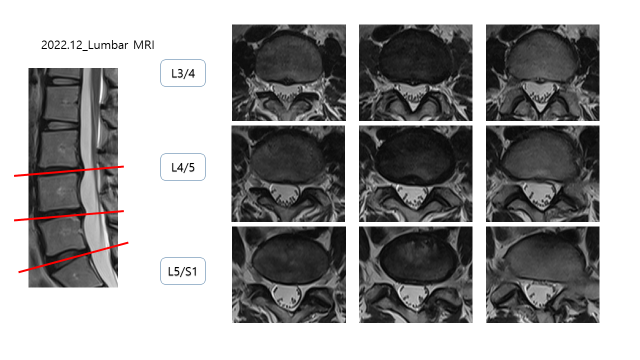

2018년도 MRI 상에서 디스크 탈출 소견이 있었음

L3/4 : DDD, Disc herniation

L4/5 : DDD, Disc protrusion

L5/S1 : bulging disc

이전에 촬영한 MRI와 비교를 하였을 때, 디스크 돌출/탈출 된 부분이 줄어든 것을 확인 할 수 있음.

환자분께 물어보니, 4년전 신경차단술을 3차례 정도하고 허리를 관리를 하였다고 하였다고 한다.

저 당시는 엄청 힘들었다고 해도 수술 안하고 버틴게 다행이라고 말씀드렸다.